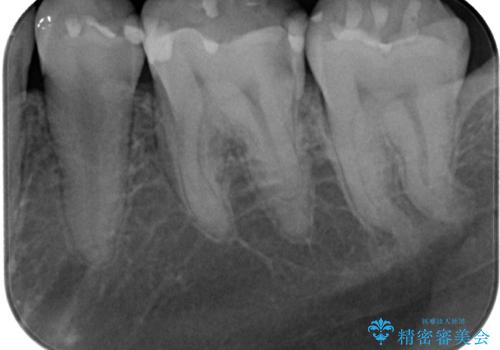

- 当院で矯正治療を終えて、左下が虫歯になっている気がするとのことで来院された患者様です。レントゲン検査の結果、コンポジットレジンによる修復箇所が複数行われており、詰め物の下に虫歯を認めました。

拡大鏡視野下でコンポジットレジン、虫歯の除去を行い、オールセラミッククラウンに適した形に整えました。